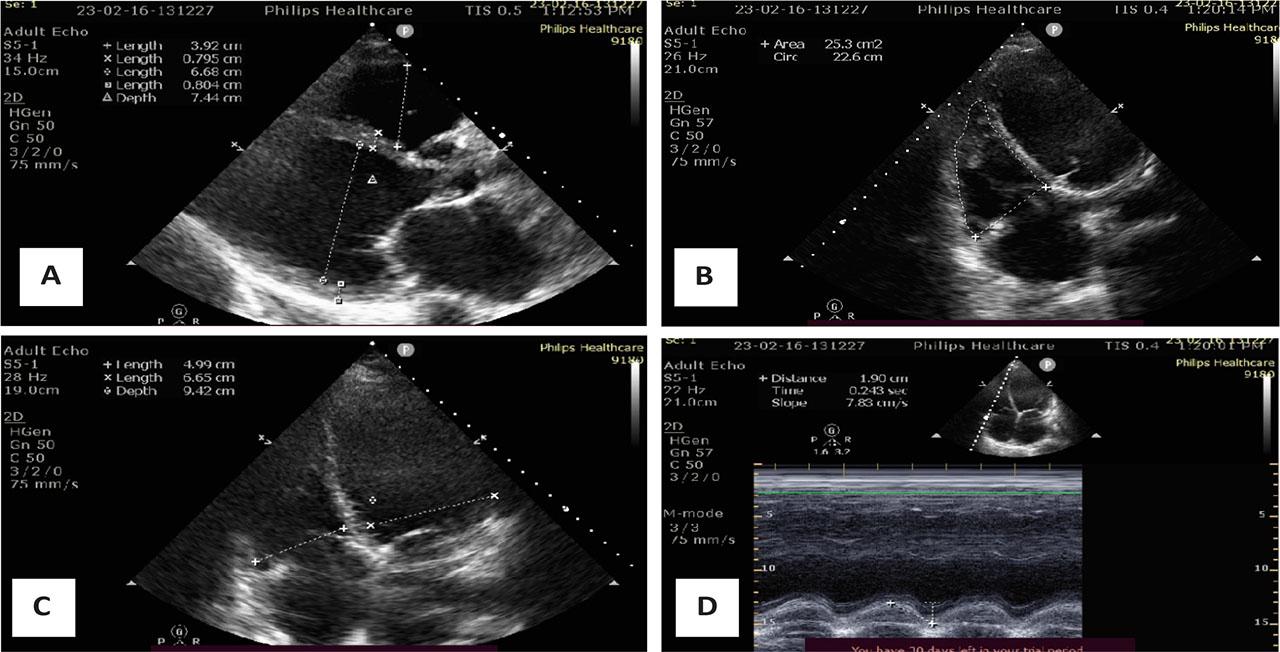

On admission, prior to LVAD implantation, transthoracic echocardiography revealed a severely dilated left ventricle (LVEDd: left ventricular end-diastolic diameter, 66 mm) with markedly reduced systolic function (LVEF: left ventricular ejection fraction by Simpson biplane, 21 %). The right ventricle was also dilated (RVED1: right ventricular end-diastolic diameter, 50 mm) with reduced systolic performance, as indicated by a tricuspid annular plane systolic excursion (TAPSE) of 16 mm and a right ventricular fractional area change (RV FAC) of 28%. Both atria were enlarged: right atrial (RA) area measured 26.5 cm2, left atrial (LA) anterior-posterior diameter was 54 mm, and the left atrial volume index (LAVI) was elevated at 59 mL/m2. Significant valvular pathology included severe tricuspid regurgitation (peak gradient: 41 mmHg) and moderate-to-severe mitral regurgitation. The estimated pulmonary artery systolic pressure was elevated, suggestive of secondary pulmonary hypertension. (Figure 2).

Transthoracic echocardiography on admission: A - Severely dilated left ventricle (LVEDD 66 mm), severely reduced ejection fraction (EF 21%); B - RV FAC – Right ventricle fractional area shortening (28%); C - RV/LV - mid linear dimension ratio in 4 chamber view (0,75); D - TAPSE – tricuspid annular plane systolic excursion (16 mm).